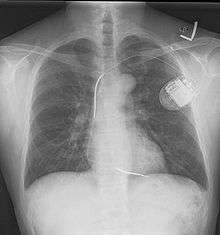

An implantable cardioverter-defibrillator (ICD) or automated implantable cardioverter defibrillator (AICD) is a device implantable inside the body, able to perform cardioversion, defibrillation, and (in modern versions) pacing of the heart. The device is therefore capable of correcting most life-threatening cardiac arrhythmias. The ICD is the first-line treatment and prophylactic therapy for patients at risk for sudden cardiac death due to ventricular fibrillation and ventricular tachycardia.[1] Current devices can be programmed to detect abnormal heart rhythms and deliver therapy via programmable antitachycardia pacing in addition to low-energy and high-energy shocks.

The process of implantation of an ICD system is similar to implantation of a pacemaker. In fact, ICDs are composed of an ICD generator and of wires. The first component or generator, contains a computer chip or circuitry with a RAM memory, programmable software, a capacitor and a battery; this is implanted typically under the skin in the left upper chest. The second part of the system is an electrode wire or wires that, similar to pacemakers, are connected to the generator and passed through a vein to the right chambers of the heart. The lead usually lodges in the apex or septum of the right ventricle. Just like pacemakers, ICDs can have a single wire or lead in the heart (in the right ventricle, single chamber ICD), two leads (in the right atrium and right ventricle, dual chamber ICD) or three leads (biventricular ICD, one in the right atrium, one in the right ventricle and one on the outer wall of the left ventricle). The difference between pacemakers and ICDs is that pacemakers are also available as temporary units and are generally designed to correct slow heart rates, i.e. bradycardia, while ICDs are often permanent safeguards against sudden life-threatening arrhythmias.

Initially ICDs were implanted via thoracotomy with defibrillator patches applied to the epicardium or pericardium. The device was attached via subcutaneous and transvenous leads to the device contained in a subcutaneous abdominal wall pocket. The device itself acts as an electrode. Most ICDs nowadays are implanted transvenously with the devices placed in the left pectoral region similar to pacemakers. Intravascular spring or coil electrodes are used to defibrillate. The devices have become smaller and less invasive as the technology advances. Current ICDs weigh only 70 grams and are about 12.9 mm thick.